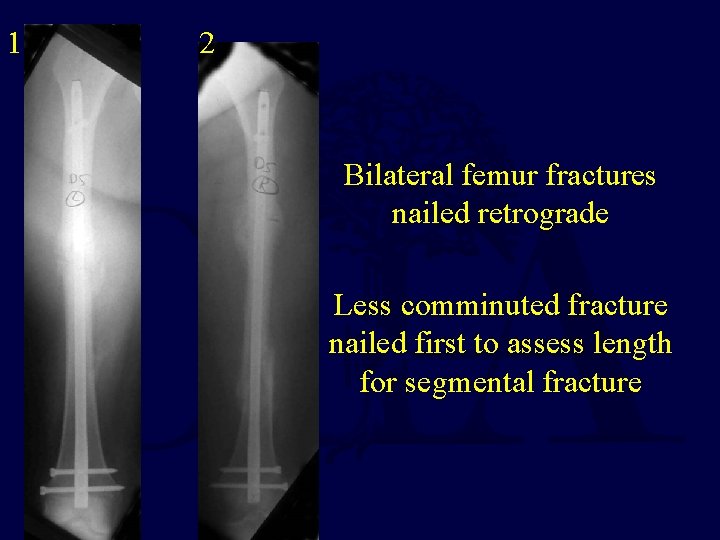

1 2 Bilateral femur fractures nailed retrograde Less comminuted fracture nailed first to assess length for segmental fracture